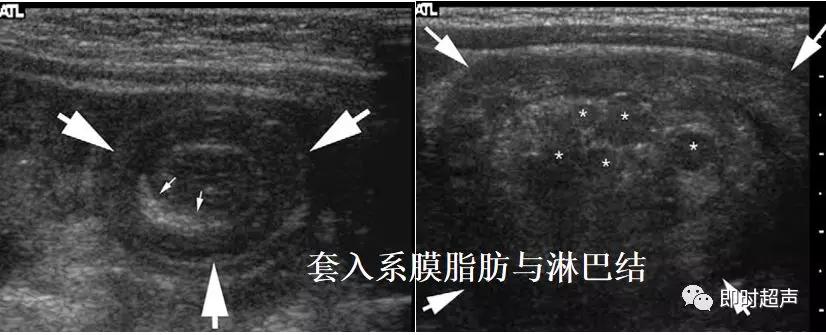

超声表现

低回声团:短轴 靶环征

长轴 套筒征

偏心 阑尾、息肉等

肠套叠超声表现

短轴切面同心圆征

长轴切面套筒征、短轴切面同心圆征